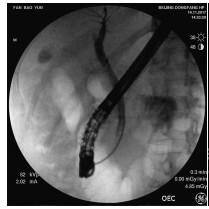

Application of transjugular liver biopsy in the diagnosis and treatment of complicated and severe liver diseases

Hua TIAN, Qiang YU, Shaoli YOU, Sa LYU, Shuhong LIU, Bing ZHU

2021, 37(12): 2874-2877. DOI: 10.3969/j.issn.1001-5256.2021.12.027

Abstract(1229) HTML (245) PDF (2586KB)(88)

Abstract:

Objective  To investigate the application value of transjugular liver biopsy (TJLB) in the diagnosis and treatment of complicated and severe liver diseases.  Methods  A retrospective analysis was performed for the clinical data of 31 patients who underwent TJLB in The Fifth Medical Center of Chinese PLA General Hospital, including indication for puncture, success rate, and final diagnosis.  Results  Among the 31 patients, there were 15 male patients and 16 female patients. Percutaneous liver biopsy was unsuitable for 8 patients with liver failure and disturbances of blood coagulation, 13 with liver cirrhosis and ascites, and 10 with liver cirrhosis and thrombocytopenia (< 50×109/L), which were the indications for TJLB. The success rate of TJLB puncture was 100%, with 2-4 passes for puncture. No serious adverse event was observed. Of all 31 patients, 26 (83.87%) had a definite diagnosis at discharge, among whom there were 5 patients with idiopathic portal hypertension, 9 patients with drug-induced liver failure or liver cirrhosis, 5 patients with autoimmune liver disease, and 7 patients with liver cirrhosis or liver failure due to other causes, and 5 patients had unknown etiology. In addition, 3 patients underwent biopsy to confirm the diagnosis and decision of whether liver transplantation should be performed.  Conclusion  TJLB plays an important role in the diagnosis and treatment of complicated and severe liver diseases and still has certain limitations, and therefore, suitable patients should be selected in clinical practice.